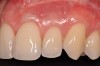

Case Report

A 24-year-old, nonsmoking man presented for correction of gingival clefting and recession in the maxillary left anterior sextant (Figure 6). The patient’s medical history was noncontributory. After consultation and presenting various options to the patient to correct the localized recession, the patient opted for the use of acellular dermal matrix tissue rather than harvesting tissue from his palatal area.

Fig 6. Pretreatment clinical view, maxillary left anterior sextant, of case presented.

Figure 6